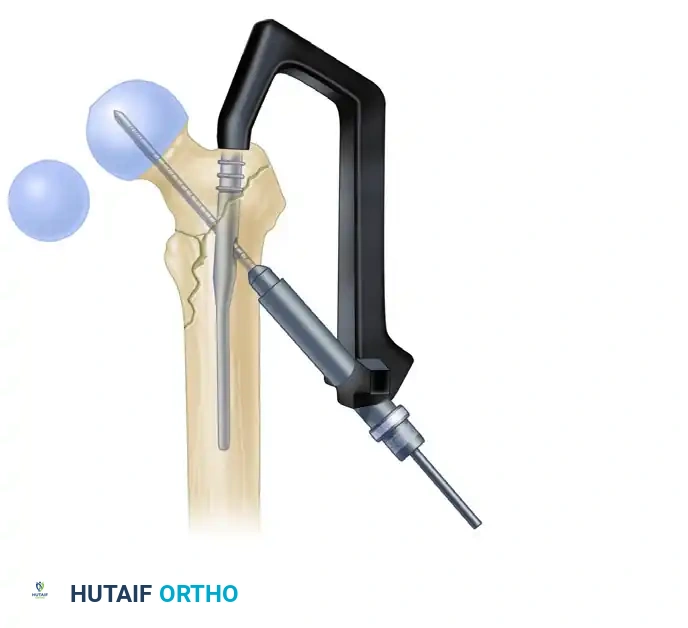

- Use the centering sleeve insertion device to advance the centering sleeve over the lag screw shaft, locking it into the nail.

- Applying Compression: Before applying compression, release the traction on the fracture table. This allows the fracture fragments to settle. Insert the compression screw through the top of the nail and apply the desired amount of linear compression across the fracture site.